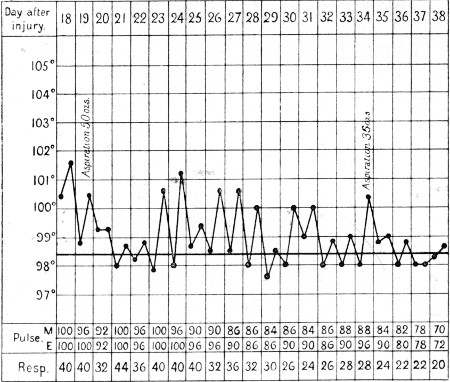

1. Case of Axillary Hæmatoma, Blood Temperature 119

2. Case of Hæmothorax with Recurrent Hæmorrhages 395

3. Primary and Secondary Rises of Temperature in Hæmothorax, Recovering Spontaneously 402

4. Secondary Rise of Temperature in Hæmothorax 403

5. Falls of Temperature in Hæmothorax following Paracentesis 404

6. Secondary Hæmothorax, Spontaneous Fall of Temperature 405